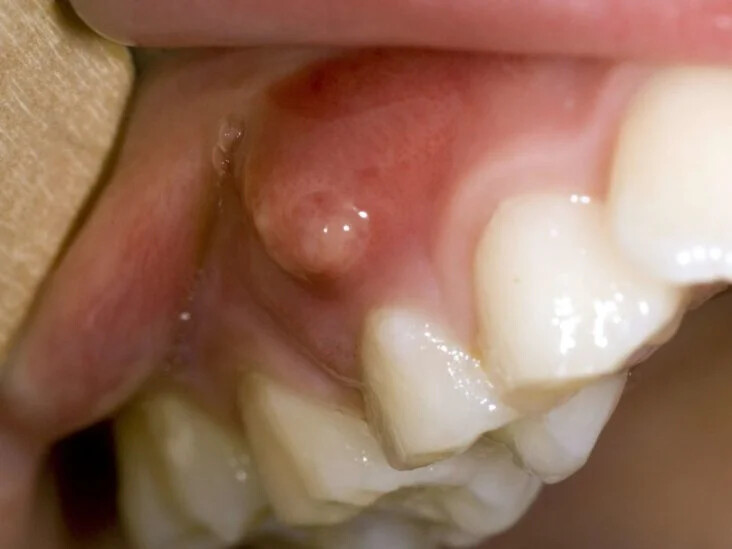

When To Receive Gum Abscess Treatment

The vast majority of gum or periodontal diseases are painless and rarely require urgent dental attention. The gum abscess is a common exception. Associated with pain that does carry a more pressing need, this acute problem will require a visit to a dentist to make the appropriate diagnosis and provide a form of gum abscess treatment that relieves your irritation. Other signs and symptoms of a gum abscess include swelling, redness, bleeding and pain when chewing.

Gingival Abscess

The first type is called a gingival abscess because it is contained in the area of the gum that is closest to the "neck" of the tooth. The tooth usually doesn't have preexisting pockets or bone loss, suggests the University of Medicine and Pharmacy of Târgu MureČ™, and often catches inflammation caused by food or foreign-body impact into the gum area around this particular tooth.

Periodontal Abscess

The second and more advanced form of gum abscess is the periodontal abscess. This is associated with a tooth that already has a periodontal pocket and a degree of bone loss. Like the gingival abscess, however, it can also be caused by food or a foreign object impacted into the pocket around the tooth. Coming on its own as your gum problem worsens, this condition can still develop after a dental cleaning where germs still overgrow despite having recently received treatment in the area.